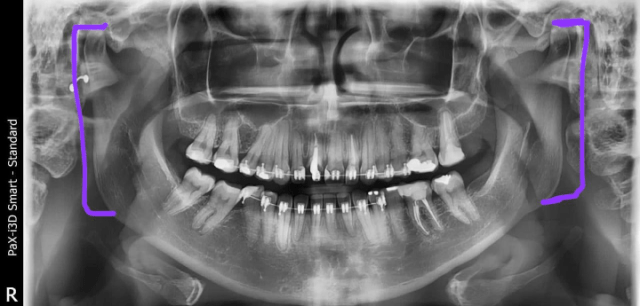

Em 2020 tive um problema na minha maxilar e nos últimos dias essas complicações tem se tornado maiores, com estralos.

As vezes quando falo ela trava e não consigo comer porque dói.

De acordo com a orientação do dentista tenho que cuidar o mais rápido possível para não ter complicações no futuro e precisar fazer uma cirurgia. Esse tratamento fica em torno de 1000 reais e apesar de não ser um valor tão alto no momento não tenho condições de arcar com todas essas despesas já que tenho outros problemas de saúde.

Tenho todos os exames para comprovar a urgência desse tratamento. Agradeço de coração sua atenção e ajuda.”